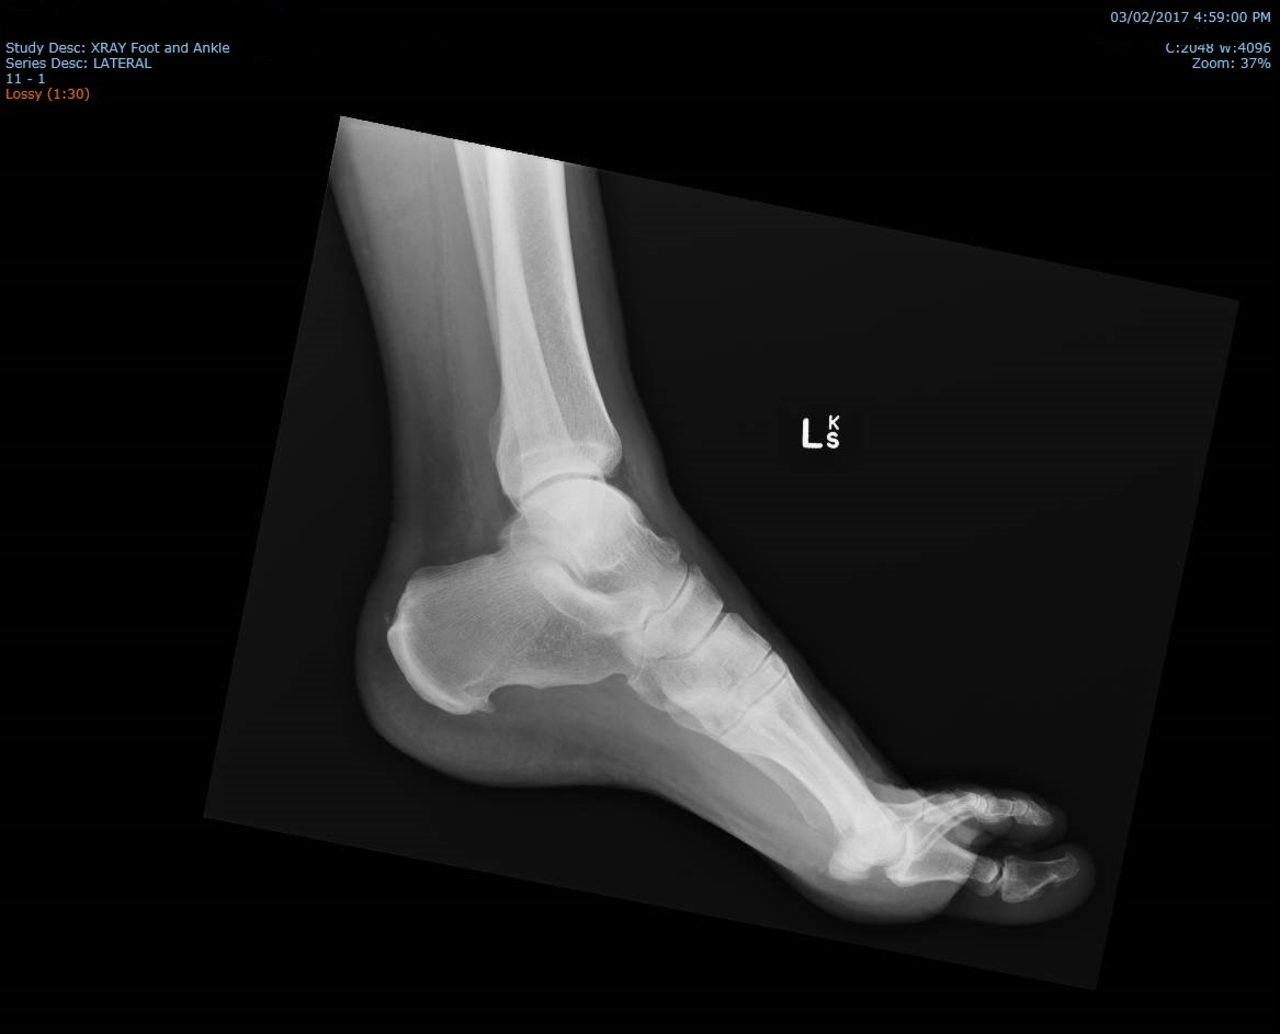

To narośl kostna, którą widzisz na zdjęciach RTG w okolicy wyrostka przyśrodkowego guza piętowego.

Jak wygląda ostroga piętowa na zdjeciu RTG - foto by IanWhyte dla Wikipedia

Aby postawić diagnozę, lekarz bada pacjenta i pyta o objawy. Zleca badanie RTG lub USG, uzyskuje bardziej szczegółowy obraz pięty.